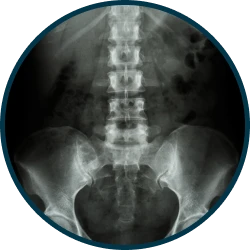

X-ray

X-ray실